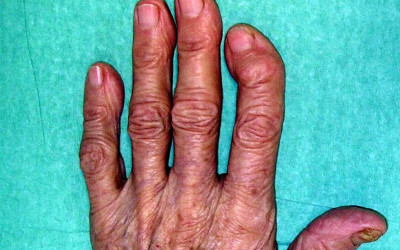

Osteoarthritis of the fingers

Created:02-03-2013 || Updated: 07-02-2020